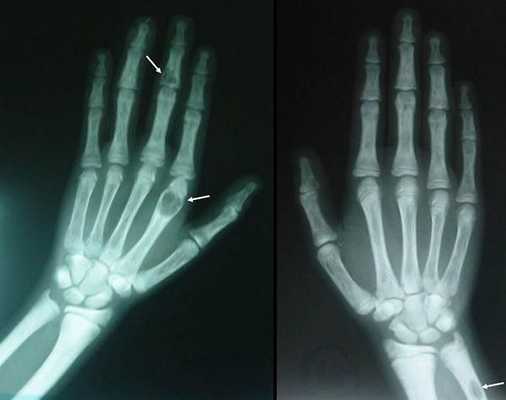

На поздней стадии костного гиперпаратиреоза происходит размягчение, искривления, патологические переломы (при обычных движениях, в постели) костей, возникают рассеянные боли в костях рук и ног, позвоночнике. В результате остеопороза челюстей расшатываются и выпадают здоровые зубы. Из-за деформации скелета больной может стать ниже ростом. Патологические переломы малоболезненны, но заживают очень медленно, часто с деформациями конечностей и образованием ложных суставов. На руках и ногах обнаруживаются периартикулярные кальцинаты. На шее в области паращитовидных желез можно пальпировать большую аденому.

Если патологический процесс в костях продолжает развиваться, это может стать причиной расшатывания и выпадения здоровых зубов, а также деформации костей скелета, в связи с которой пациенты становятся ниже ростом. Возникающие переломы очень медленно восстанавливаются, часто с деформациями р ук и ног и образованием непрочных суставов. На конечностях появляются кальцинаты — результат отложения солей.

- костный гиперпаратиреоз — де формация конечностей, внезапные переломы, возникающие как бы сами по себе, остеопороз с возможными кистозными образованиями, болезнь Реклингхаузена;

- разрушение дистальных или концевых фаланг конечностей;

- сужение дистального отдела ключиц;

- очаги разрушения костей черепа;

- бурые опухоли длинных костей.